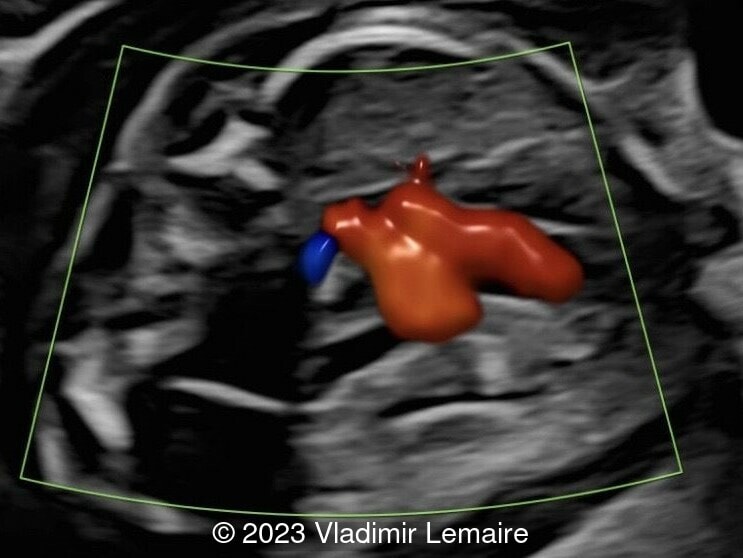

Aberrant right subclavian artery, seen in red, in a fetus at 20 weeks of gestation.

Image 3 Aberrant right subclavian artery, seen in red, in a fetus at 20 weeks of gestation.